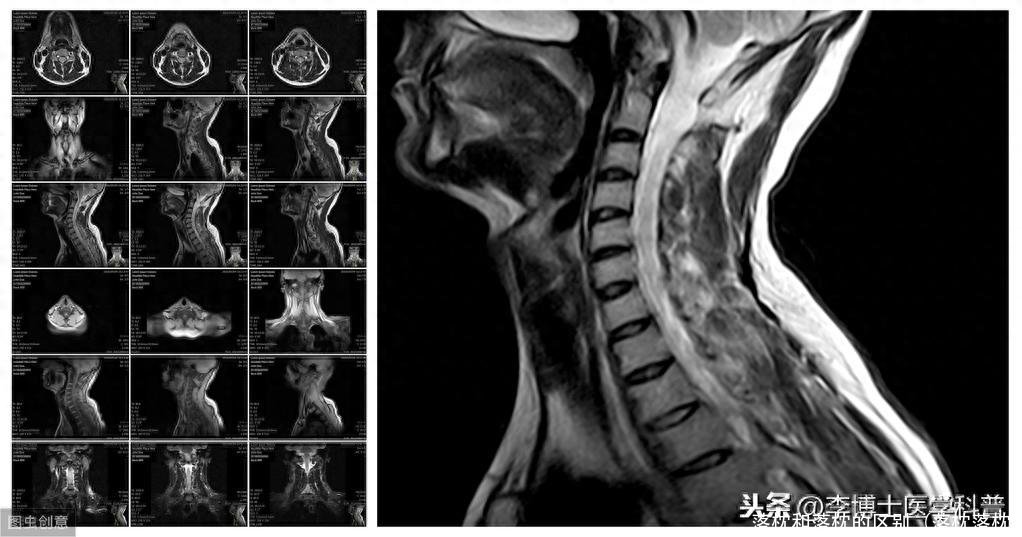

落枕,现代医学上称为急性颈椎关节周围炎,往往是由于颈部受凉、过度劳累、睡眠姿势不当、枕头高低软硬不合适等原因,使颈部肌肉遭受长时间的过分牵拉而发生异常收缩或痉挛,一般认为是颈椎病的先兆。

很多人认为落枕不是病,不处理也会好转,不必加以重视,这其实是个误区。落枕的发生提示颈椎周围的韧带、肌肉已有松弛,丧失了维持颈椎稳定性的能力,这种不稳定可以累及椎间盘,导致骨质增生,椎间盘退变,进而发展成颈椎病。落枕,尤其反复发作,逐渐加重,一年内发生三四次甚至更多,这种情况需要去正规医院就诊拍片,评估骨性的颈椎曲度以及椎间盘的形态。

颈椎病是一种颈椎退行性脊椎病,多发病于40岁以上的劳动者,其病因常常因颈部反复挫伤及劳损造成颈椎逐渐出现一系列的病理变化,发病后出现颈项、肩臂、肩胛上背、上胸壁及上肢疼痛为主要要特征的十种慢性:复发性的中、老年病。疼痛的特点以劳累过度或受寒而加剧,疼痛的部位多与颈椎有密切关系。病程较长,不易根除。 落枕是一种颈项酸痛、转动不利的一种疾病,常因睡眠时姿势不正或颈项部着凉,感受风寒而致气血失调、经络受阻而造成颈部一侧肌群拘急疼痛,活动不利或受限。病程较短,治疗及时,可很快治愈。

☆醒来脖子僵就是落枕吗☆

晨起后的颈项僵硬酸痛和活动受限不一定都是落枕引起的。但如果这些症状经常发生,并且症状在一周内无法消失,那么应当重视,可能是患有颈椎病。这种情况可能由原有的颈椎病自身引起,也可能是由于频繁落枕造成的颈椎周围肌肉韧带松弛,颈椎关节稳定性下降,甚至可能发生小关节错位,进而频发脖子酸痛。如果在这种症状的基础上出现了上肢或下肢麻木发凉、头痛头晕、恶心等症状,那么更应该加以警惕,需及时前往医院就诊,在骨科接受检查和治疗。